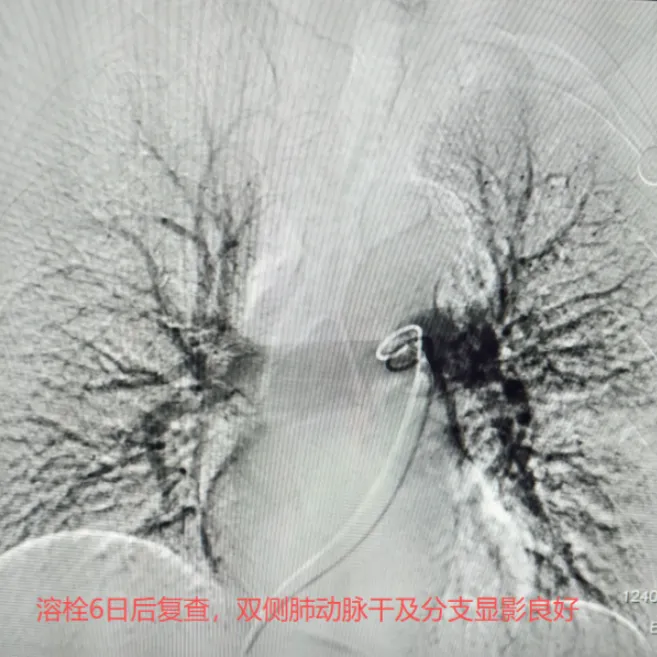

经过6天规范化的后续溶栓治疗,复查造影显示,患者肺动脉血流已完全恢复,栓塞征象消失。在后续抗凝治疗的巩固下,患者恢复情况良好。此例危重肺栓塞患者的成功救治,充分彰显了略阳县人民医院在多学科协作(MDT)模式下救治急危重症患者的强大综合实力。